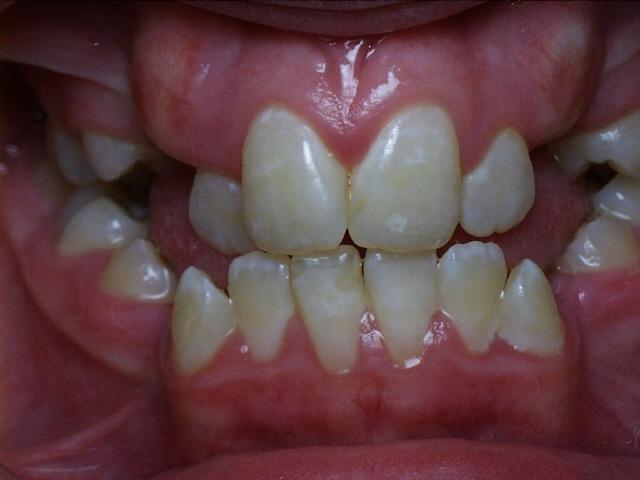

Moderate crowding with a severe overbite.  Treatment time was 20 months.  This case required the extraction of two upper permanent teeth.  The molars were class 2 (upper molars too far forward at the start of treatment).